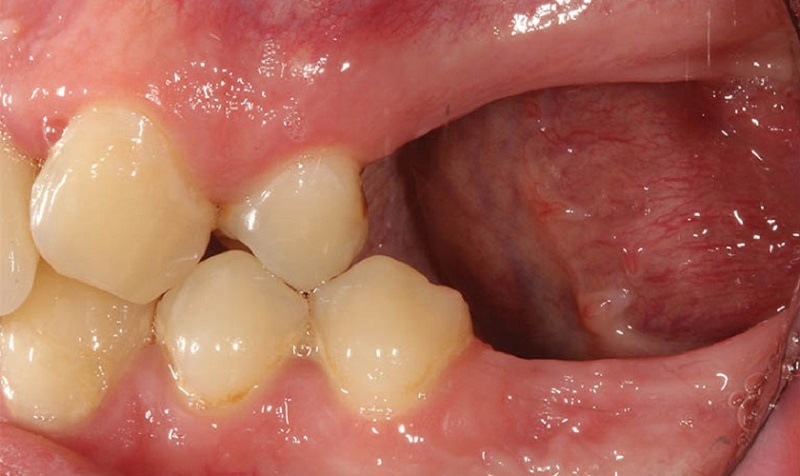

Để khoảng trống quá lâu có thể bị tiêu xương

3. Nếu để quá lâu mới trồng lại răng cấm thì sao?

Nếu để quá lâu không trồng răng cấm, khoảng trống mất răng khiến các răng kế cận dần nghiêng đổ, phá vỡ khớp cắn và khiến việc ăn nhai kém ổn định. Xương hàm tại vị trí này cũng bị tiêu dần do không còn lực kích thích, dẫn đến hóp má, khuôn mặt lão hóa nhanh và thiếu cân đối.

- Răng xô lệch, mất ổn định khớp cắn: Các răng lân cận sẽ từ từ nghiêng vào khoảng trống mất răng, gây lệch lạc toàn hàm và làm tăng nguy cơ lung lay răng thật.

- Tiêu xương hàm, gương mặt lão hóa: Xương hàm không được kích thích bởi lực nhai sẽ teo lại, khiến má hóp, da mặt chảy xệ và khuôn mặt trông già hơn tuổi.